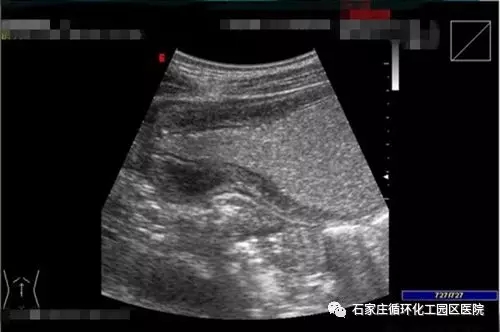

胃腸超聲造影檢查是通過一種助顯劑(口服或灌腸)充盈胃腸腔,能夠消除胃腸腔內(nèi)氣體、內(nèi)容物等對超聲波的干擾,而本身又不影響超聲波的穿透,改善了胃腸超聲成像的內(nèi)環(huán)境,使聲束能順利穿透,從而達(dá)到使胃腸壁結(jié)構(gòu)及其病變能更加清晰顯示的一種方法。

胃腸超聲造影通過胃腸超聲助顯劑提高胃腸成像質(zhì)量,明顯提高病灶的顯示率、檢出率,是胃腸不適患者檢查的新選擇,成為內(nèi)窺鏡檢查的有益補(bǔ)充,可用于胃腸不適患者的篩查。